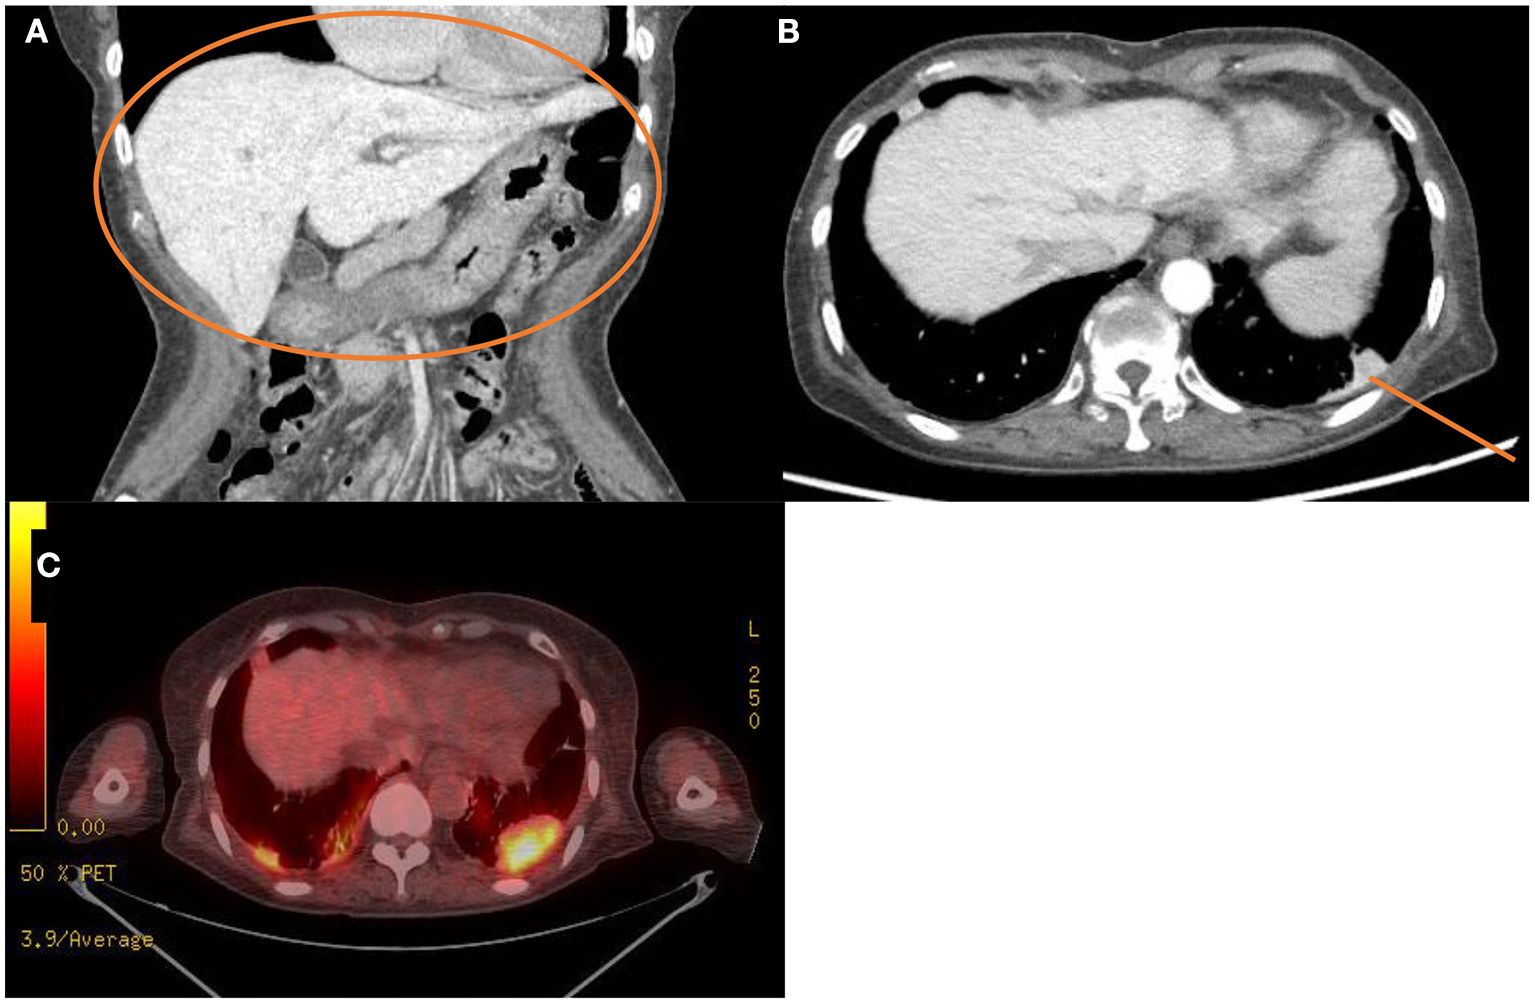

The laboratory workup showed that the level of the total bilirubin was 0.71 mg/dL (reference range, 0.22–1.3), the aspartate aminotransferase level was 358 U/L (reference range, 10–37), the alanine aminotransferase level was 177 U/L (reference range, 10–37), and the prothrombin time was 1.90 International Normalized Ratio (INR) (reference range, 0.8–1.2). Enhanced computed tomography (CT) showed diffusely increased liver intensity and scattered hyper attenuated nodular consolidations in the subpleural areas of both lungs (Figures 1A,B). To evaluate the possibility of malignancy, positron emission tomography–CT (PET–CT) was performed, and multiple hypermetabolic lesions (maximal standardized uptake values 7.3, Figure 1C) were examined. To confirm the diagnosis of the lung lesions, transthoracic needle biopsy was performed, and the pathologic examination showed fibrinoid interstitial inflammation with atypical change of type II pneumocytes and intra-alveolar foamy macrophages (Figure 2). Using both the CT and biopsy findings, we could diagnose the amiodarone-induced hepatic and pulmonary toxicity.

Figure 1

Radiologic findings of the abdominal cavity and the chest. (A,B) Initial computed tomography scan of the abdominal cavity and the chest. This scan shows diffuse increased liver intensity [(A), orange circle] and scattered hyperattenuation nodular consolidations in the subpleural areas of both lungs [(B), orange line]. (C) Fluorodeoxyglucose positron emission tomography–computed tomography scan of the whole body showing about 4.8 cm hypermetabolic lesion in the left lung field (maximal standardized uptake, 7.3).